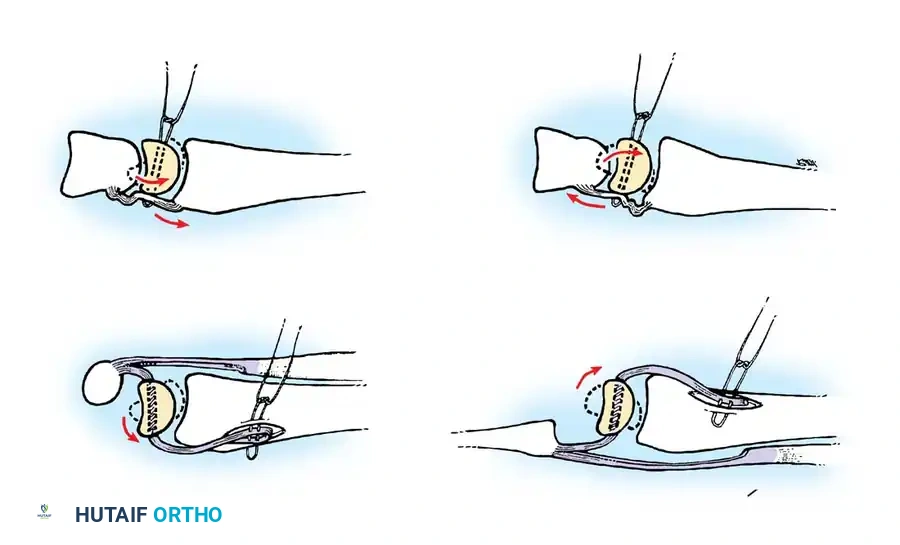

Closed reduction with percutaneous pinning (placing 0.045-inch K-wires from the scaphoid to the capitate and lunate) can be attempted. However, open reduction through a dorsal approach is generally preferred. This allows direct closure of the scapholunate gap, K-wire fixation, and primary repair of the dorsal SL interosseous ligament using suture anchors.